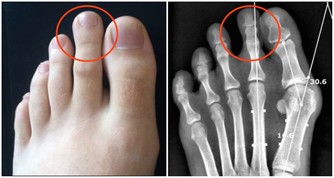

1. 血液循環不良

血液循環不佳是導致手腳冰冷的主要因素之一。當身體的血液無法順利輸送到四肢時,手腳的溫度自然會降低。長時間久坐、缺乏運動、血管收縮等都會影響血液循環,使得四肢末端容易變冷。